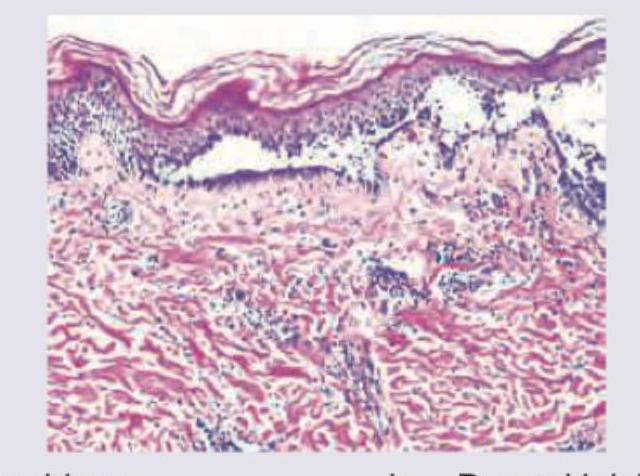

Question 2: What is the diagnosis based on the image shown below?

- C. Mycosis fungoides (Correct Answer)

Explanation: ***Mycosis fungoides*** - The image exhibits **Pautrier microabscesses**, which are collections of atypical lymphocytes within the epidermis, a hallmark of mycosis fungoides. - There is also a **band-like infiltrate of atypical lymphocytes** in the upper dermis, characteristic of this cutaneous T-cell lymphoma. *Pemphigus* - Pemphigus is characterized by **intraepidermal blistering due to acantholysis** (loss of cohesion between keratinocytes), which is not seen in this image. - Histology would show separated keratinocytes, often with a "tombstone" appearance of basal cells, and **no Pautrier microabscesses**. *Dermal leishmaniasis* - Dermal leishmaniasis is caused by _Leishmania_ parasites and typically presents with a **dermal infiltrate rich in macrophages** containing intracellular amastigotes. - The image does not show these features; instead, it shows an atypical lymphoid infiltrate. *Psoriasis* - Psoriasis typically shows **acanthosis (epidermal hyperplasia)** with elongation of rete ridges, **parakeratosis**, and **Munro microabscesses** (neutrophilic collections in the stratum corneum). - While there is some epidermal thickening, the distinct Pautrier microabscesses and atypical lymphoid infiltrate are not features of psoriasis.